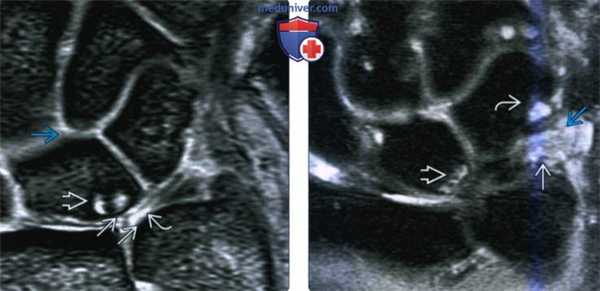

(Слева) На фронтальной МРТ GRE определяется центральная перфорация треугольного фиброзно-хрящевого комплекса и потеря хряща головки локтевой кости и проксимальной поверхности полулунной кости с кистозными изменениями. Полулунно-трехгранная связка интактная. Полулунная кость II типа.

(Справа) На фронтальной МРТ в режиме STIR определяется типичная картина импичмента шиловидного отростка локтевой кости с отеком в шиловидном отростке локтевой кости и по периферии трехгранной кости и синдрома легкого сдавливания локтевой кости. Имеется синовит в прешиловидных мягких тканях.